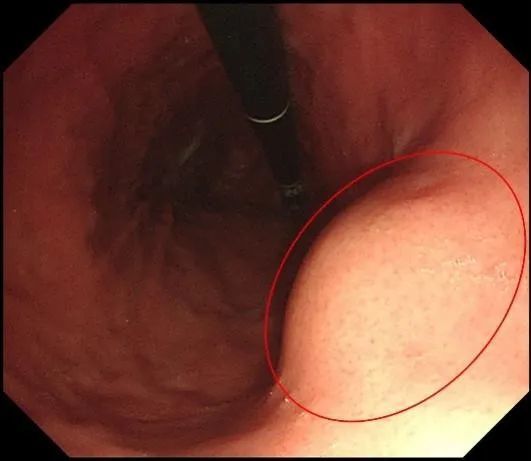

最近,冯阿姨总感觉胃不舒服,于是,在医生的建议下做了一个胃镜,突然发现胃里长了个小东西(如下图),随后,在熟人的介绍下,冯阿姨在家人的陪同下来河南省肿瘤医院普外科就诊,顺利完成手术,术后病理证实为胃肠间质瘤。

(左)胃镜显示粘膜完整,呈隆起型病变